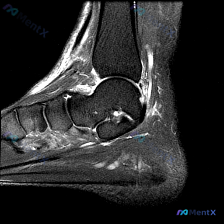

今天分享一例踝关节矢状位T2序列MRI的读片病例,整理了完整分析思路,和大家一起讨论。 病例影像基本信息 检查部位:踝关节MRI-T2序列-矢状位 可见解剖结构:胫骨远端、距骨、跟骨及部分跗骨 核心影像异常表现 1. 骨组织:距下关节跗骨窦区可见高信号影,距下关节面上方伴异常液体信号;跟骨内部靠近跖...